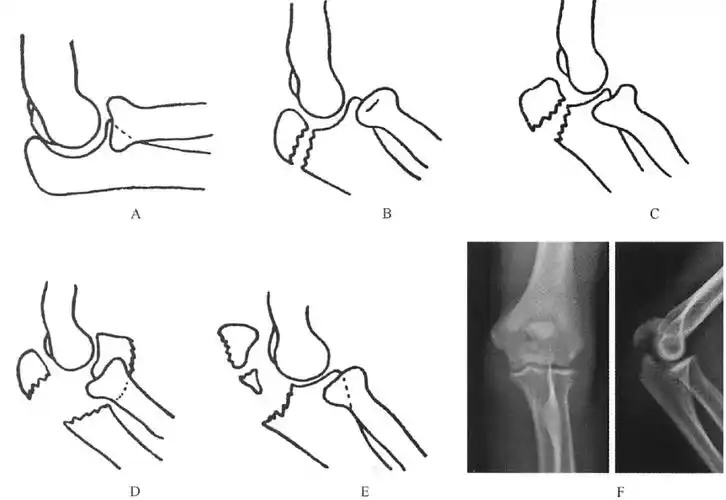

肱骨髁上骨折分型